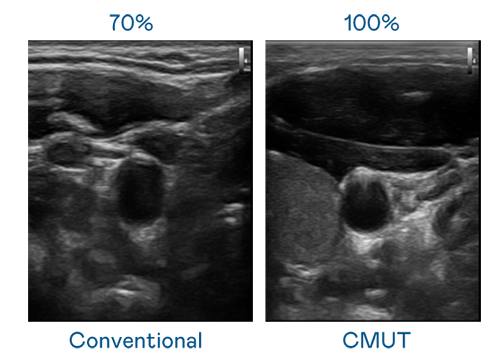

CMUT 技术是一种用电容式微机电元件来产生超音波讯号的技术。与传统 PZT 压电式技术相比,CMUT 频宽增加 30%,更宽频的超音波讯号让影像解析度大幅提升,是实现高影像品质医疗超音波扫描、促进精准医疗发展的关键技术。

大频宽带来超清晰影像

超音波影像的解析度高低,首先取决于探头能发出的讯号频宽。新七擒七纵七色狼的曹查理 CMUT 可提供高清晰的超音波讯号,提供高频宽、高灵敏度、影像纹理细节更高的超音波影像,协助医护人员缩短影像判读时间及利用精准的医疗影像进行诊断。